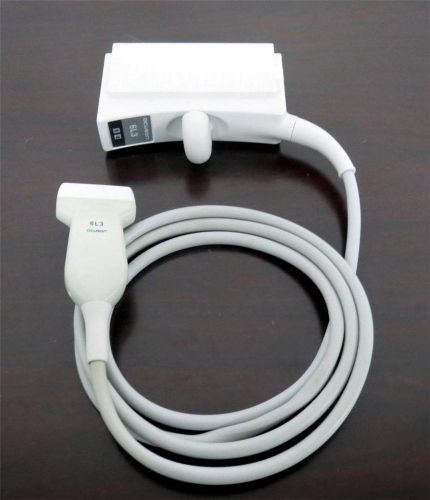

Acuson 6L3 Transducer Ultrasound Vascular Probe for Acuson Sequoia WARRANTY #1